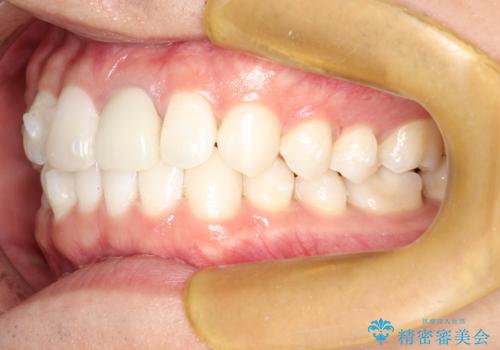

インビザラインによる矯正治療(非抜歯) 下の前歯の歯並びの改善

- 主に下の歯並びの改善を主訴としてご来院されました。

右下の犬歯と前歯が大幅に重なっているのと、歯の向きも大きく横に倒れています。この部位の正常な配列のためには、3次元的に大幅な移動が必要となりました。

インビザラインの特色を生かした歯牙移動計画を作成し、非抜歯にて治療を行いました。

概ね1年弱で治療が完了しました。

前歯の大きな3次元的移動を可能にするために、当院独自の工夫を随所に盛り込み、狙い通りの治療結果を得られました。